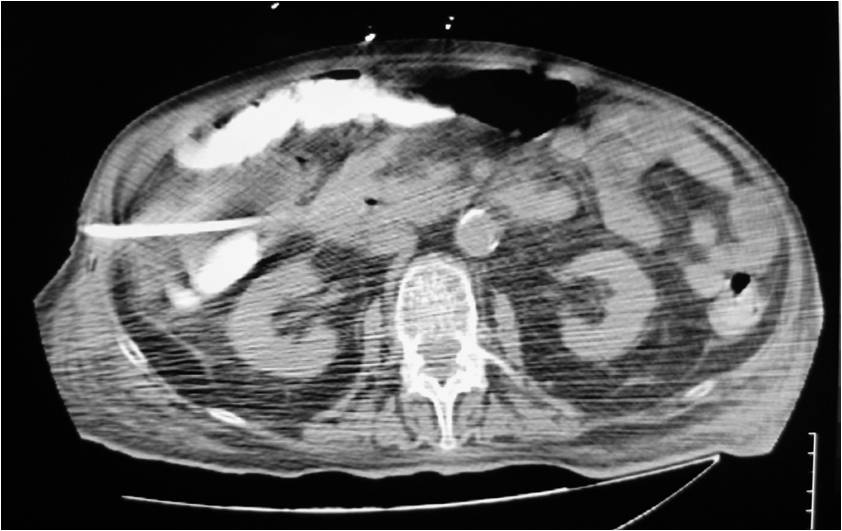

PATIENTS AND METHODS: During the last two and a half years, 93 post-operative patients were referred to the CT department for drainage of a post-surgical abscess in the abdomen or pelvis at 9-21 days post-operatively due to persistent fever. A total of 95 abscesses were drained; 84 were located in the abdomen and 11 in the pelvis. Abscess diameters ranged between 2 and 12 cm. A percutaneous drainage technique under CT-guidance was employed in all patients; 98 catheters were placed with use of the Seldinger technique. A transgluteal paracoccygeal approach was adopted in 11 patients. Aspiration of an intra-loop abscess was performed in 1 patient. The tilted gantry technique was utilized in 2 cases.

- Placement of a nephrostomy and sump caheter through the greater sciatic foramen into a deep pelvic abscess.